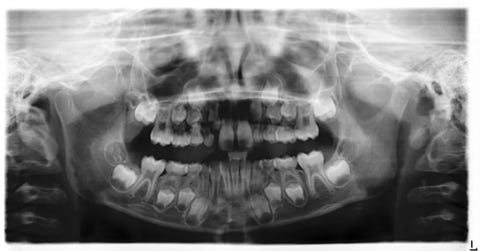

Een behandeling start met een intake, gevolgd door röntgenfoto’s en afdrukken. Daarna maakt de beugel specialist een plan. Tijdens het traject zijn er regelmatige controles in de orthodontie kliniek.